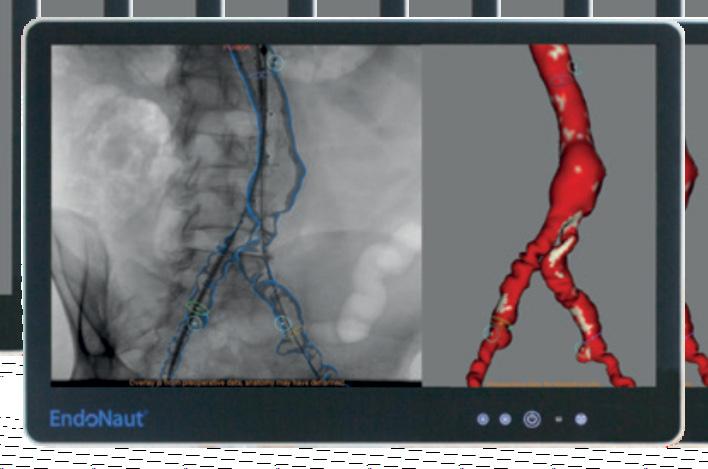

Revascularizarea hibridă, un element important în arsenalul chirurgului vascular

Boala arterială periferică (BAP) reprezintă afectarea țesuturilor periferice din cauza aterosclerozei, prin privarea de oxigen a acestora. În populația generală are o incidență de 11.8% și, din totalul de pacienţi diagnosticaţi, aproximativ jumătate sunt asimptomatici[1]. Aceasta ar putea explica infra-managementul terapeutic sau deficitul de pacienţi diagnosticaţi la controalele medicale de rutină, pacienții prezentânduse ulterior la medic cu forme avansate ale bolii, cu un risc crescut de amputație.

Medic sp. ch. cv., Inst. „Prof. Dr. George I.M. Georgescu” Iași, Drd. la UMF „G.T. Popa” Iași

Persoanele cu vârsta mai mare de 75 de ani au o prevalență sem nificativ mai mare pentru BAP (31.6 - 37.2/1000 persoane/an) raportat la populația cu vârsta cuprinsă între 65-74 de ani (16.2 – 21.7/1000 per soane/an)[1]. Simptomele BAP pot fi diza bilitante și pot evolua până la pierderea unui membru. Afecțiunea este asociată cu o incidență crescută pentru infarctul miocardic, accident vascular cerebral și deces. Incidența în populația generală a ischemiei critice a membrului inferior este aproximativ 1%, dar simptomatolo gia clinică și natura letală aduc o rată de mortalitate ce poate ajunge pană la 50% la 5 ani și 70% la 10 ani[3]

Revascularizarea arterială reprezintă terapia standard, unanim acceptată de că tre comunitatea științifică internaţională, în ceea ce privește prevenția amputaţiilor.

Opțiunile moderne de revascularizare includ tehnicile endovasculare, chirur gicale și revascularizarea hibridă (ca o combinație între procedeele chirurgicale și endovasculare)[6]. Există în ultimii ani o tendință generalizată de aplicare pe sca ră largă a abordului primar endovascular, datorat preponderent invazivității, riscu lui crescut de morbiditate și mortalitate asociate chirurgiei de revascularizare și, nu în ultimul rând, progreselor tehnice în domeniul endovascular.

Ambele metode de revascularizare, endovascular și chirurgical, îndeplinesc un rol important în tratamentul pacien ților cu boală arterială periferică. În ab sența revascularizării arteriale, studiile relevă că, la 6 luni de la diagnosticarea bolii, până la 40% dintre pacienți, riscă o amputație majoră[3]. Un alt studiu ara tă că între 5,7% și 11,5% dintre pacienții amputați unilateral, beneficiază de ampu tarea membrului controlateral în primii 5 ani[13]. Fiecare intervenție trebuie efectu ată în fereastra de timp adecvată și cu un raport risc-beneficiu favorabil. În vederea realizării unei intervenţii de revascularizare, un abord multidisci plinar este necesar (chirurg vascular, ane stezist, cardiolog, nefrolog și diabetolog), deoarece majoritatea pacienţilor cu BAP, au multiple comorbidităţi asociate. Ate rosleroza este un proces patologic com plex și presupune înțelegerea extensivă a afecțiunii, și utilizarea concomitentă a mijloacelor medicale, endovasculare și chirurgicale, în favoarea colaborării și nu a competiției medicale.

În ceea ce ține de revascularizarea chirurgicală, permeabilitatea la cinci ani a bypassurilor periferice variază în func ție de anatomia acestora și de tipul de

grefon utilizat, cu o patență de la 85.2% (rata de patenţă primară) la 88.2% (rata de patenţă secundară) în cazul grefonului venos autolog, și de la 64.5% (rata de pa tenţă primară) la 79.0% (rata de patenţă secundară) pentru grefonul sintetic[2]

Referitor la tratamentul endovascu lar, un studiu prospectiv realizat pe 993 de pacienți consecutivi cu diabet zaharat, la care s-au practicat procedee endovas culare de primă intenție, a demonstrat o permeabilitate primară la de 88% 5 ani[7]

Pentru tratamentul BAP, analiza com parativă a procedeelor endovasculare și chirurgicale a fost făcută cu ajutorul unui studiu randomizat controlat, care a de monstrat rezultate similare pentru cele două grupuri, referitoare la intervalul liber de amputare precum și la calitatea vieții pacienţilor pe termen lung[10]. Alte studii au oferit rezultate similare pentru analiza comparativă între cele două teh nici[5,8,11,12]

Obiectivele terapeutice urmăresc diminuarea simptomatologiei dureroa se de natură ischemică, prevenirea am putaţiilor, ameliorarea calității vieții și creșterea ratei de supraviețuire. Identi ficarea și modificarea factorilor de risc (fumatul, hipertensiunea arterială, dis lipidemia și diabetul zaharat) constituie obiective esențiale în tratamentul bolilor aterosclerotice periferice. Factorii de risc pentru dezvoltarea și evoluţia bolii arteri ale periferice sunt similari cu cei pentru boala arterială coronariană[4], acesta fiind un motiv important pentru investigarea cardiologică riguroasă preoperatorie a pacienţilor.

În boala aterosclerotică periferică, abordul endovascular, diagnostic și tera peutic a crescut în popularitate în ultime

32 www.revistamedicalmarket.ro Articole de specialitate

Masa radiotransparenta imagiQ2 este cea mai buna optiune pentru procedurile minim invazive precum chirurgia cardiovasculară, managementul durerii, electrofiziologie și neurochirurgie unde precizia și imagistica de înaltă calitate sunt critice.

Pozitionare rapida si usoara cu ajutorul Joystick ului.

Tehnologia True Free Float® permite cele mai ample deplasari longitudinale si transversal

Tehnologia EnablerTM permite reducerea dozei de radiatie cu pana la 60%.

Cea mai buna radiotransparenta a blatului mesei.

Miscarea ISO ROLL® asigura mentinerea focalizarii imaginii pe tot parcursul miscarii

Designul mesei permite plasarea bratului C mai aproape de pacient

office@accuris.ro;

le 2 decenii, literatura de specialitate pu blicând multe studii, uni sau pluricentri ce care pledează în favoarea acestui tip de tratament luând în considerare creșterea calității vieții și prelungirea intervalului liber de amputare în primii 1-3 ani după intervenție.

În ceea ce privește costurile intraspi talicești raportate la chirurgie, acestea au fost mult mai mari comparativ cu angi oplastiile. Cu toate acestea, evaluarea pe termen lung și analiza pe subgrupuri po pulaționale pledează în favoarea chirur giei ca fiind cea mai bună opțiune terape utică la pacienții cu grafturi venoase sufi ciente pentru bypass, în ciuda numărului în scădere de intervenții chirurgicale datorită creșterii incidenței intervențiilor endovasculare și a eficacității terapeutice.

Studii contemporane arată că, la mo mentul actual, nici pentru pacienții tineri nu există un consens în vederea alegerii tipului revascularizare ales[14].

Mortalitatea perioperatorie precoce asociată procedeelor de revascularizare chirurgicală a fost estimată între 1 și 2%, iar mortalitatea la 1 an, la 10%[9]

Revascularizarea hibridă constituie o opțiune viabilă la pacienții cu afectare arterială multietajată sau care au un risc înalt de complicaţii majore asociate chirurgiei. Procede ele de revascularizare hibridă sunt mai puțin invazive, au o durată mai mică şi risc scăzut de complicații perioperato rii. Acestea constituie opțiuni atractive de revascularizare şi în cazul pacienților vârstnici, fragili, sau care nu pot bene ficia de intervenţii chirurgicale majore.

Selecția procedeelor de revasculariza re variază după diferiți parametri cum ar fi lungimea, gradul și localizarea leziuni lor stenotice. Dificultatea, riscurile și pro gnosticul diferitelor proceduri depind de statusul clinic general și de comorbidități care determină, implicit, speranța de via ță a pacienților. Pacienții cu comorbidități severe nu sunt eligibili pentru revascula rizare chirurgicală sau anestezie genera lă. Procedeele endovasculare, sau chiar

management conservator, sunt elective la pacienții fragili sau chiar imobili. Criteriile de eligibilitate a procedeelor de revascularizare, chirurgicală sau en dovasculară, sunt puternic controversate în literatura de specialitate ceea ce face ca actualmente să nu existe un consens privind indicațiile sau contraindicații le tipului de revascularizare. În general, alegerea modalității terapeutice depinde de caracteristicile pacientului și de nive lul de performanță tehnică a centrului în care se efectuează revascularizarea.

Bibliografie

1. Kalbaugh CA, Kucharska-Newton A, Wruck L, Lund JL, Selvin E, Matsushi ta K, Bengtson LGS, Heiss G, Loehr L. Peripheral Artery Disease Prevalen ce and Incidence Estimated From Both Outpatient and Inpatient Set tings Among Medicare Fee-for-Ser vice Beneficiaries in the Atheros clerosis Risk in Communities (ARIC) Study. PMID: 28468784

2. Keun-Myoung Park, Young Wook Kim, Shin-Seok Yang, and Dong-Ik Kim Comparisons between prosthe tic vascular graft and saphenous vein graft in femoro-popliteal by pass. PMID: 25025025

3. Management of peripheral arteri al disease (PAD). TransAtlantic In ter-Society Consensus (TASC). PMID: 10957904

4. Andrew W. Gardner and Azhar Afaq. Management of Lower Extremity Peripheral Arterial Disease. PMID: 19008688

5. Crystal M. Botham, William L. Ben nett, John P. Cooke. Clinical Trials of Adult Stem Cell Therapy for Periphe ral Artery Disease. PMID: 24298310

6. Lee SC, Joh JH, Chang JH, Kim HK, Kim JY, Park K, Hong KC, Byun SJ, Lee TS, Jung HJ, Lee SS. Hybrid treat ment of multilevel revascularization in patients with peripheral arterial disease - a multi-centre study in Ko rea. PMID: 29484958

7. Faglia E1, Dalla Paola L, Clerici G, Cle rissi J, Graziani L, Fusaro M, Gabrielli L, Losa S, Stella A, Gargiulo M, Mante ro M, Caminiti M, Ninkovic S, Curci V, Morabito A. Peripheral angioplasty as the first-choice revascularization procedure in diabetic patients with critical limb ischemia: prospective

study of 993 consecutive patients hospitalized and followed between 1999 and 2003. PMID: 15878541

8. Romiti M, Albers M, Brochado-Neto FC, Durazzo AE, Pereira CA, De Luc cia N. Meta-analysis of infrapopliteal angioplasty for chronic critical limb ischemia. PMID: 18372148

9. Conte MS, Bandyk DF, Clowes AW, Moneta GL, Seely L, Lorenz TJ, Na mini H, Hamdan AD, Roddy SP, Bel kin M, Berceli SA, DeMasi RJ, Samson RH, Berman SS; PREVENT III Investi gators. Results of PREVENT III: a mul ticenter, randomized trial of edifoli gide for the prevention of vein graft failure in lower extremity bypass surgery. PMID: 16616230

10. Bradbury AW, Adam DJ, Bell J, For bes JF, Fowkes FG, Gillespie I, Ruc kley CV, Raab GM; BASIL trial Partici pants. Bypass versus Angioplasty in Severe Ischaemia of the Leg (BASIL) trial: An intention-to-treat analy sis of amputation-free and overall survival in patients randomized to a bypass surgery-first or a balloon angioplasty-first revascularization strategy. PMID: 20435258

11. Taha AG, Byrne RM, Avgerinos ED, Marone LK, Makaroun MS, Chaer RA. Comparative effectiveness of endo vascular versus surgical revascula rization for acute lower extremity ischemia. PMID: 25080883

12. Ohmine T, Iwasa K, Yamaoka T. Stra tegy of Revascularization for Critical Limb Ischemia Due to Infragenicular Lesions-Which Should Be Selected Firstly, Bypass Surgery or Endovas cular Therapy? PMID: 26730251

13. Glaser JD, Bensley RP, Hurks R, Da hlberg S, Hamdan AD, Wyers MC, Chaikof EL, Schermerhorn ML. Fate of the contralateral limb after lower extremity amputation. J Vasc Surg. 2013 Dec;58(6):1571-1577.e1. doi: 10.1016/j.jvs.2013.06.055. Epub

2013 Aug 3. PMID: 23921246; PM CID: PMC3844063.

14. Lepäntalo MJ, Houbballah R, Raux M, LaMuraglia G. Lower extremity bypass vs endovascular therapy for young patients with symptomatic peripheral arterial disease. J Vasc Surg. 2012 Aug;56(2):545-54. doi: 10.1016/j.jvs.2012.06.053. PMID: 22840905.

34 www.revistamedicalmarket.ro

Un nou orizont în abordarea patologiilor cardiovasculare ș i neurologice